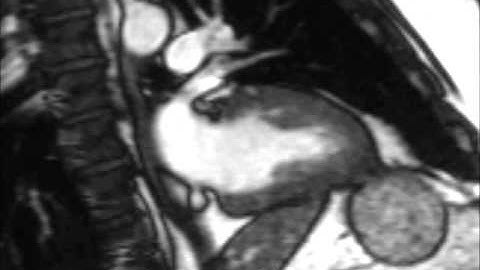

Create Left Atrial Models with Fibre Orientations using CemrgApp (Manual Pipeline)